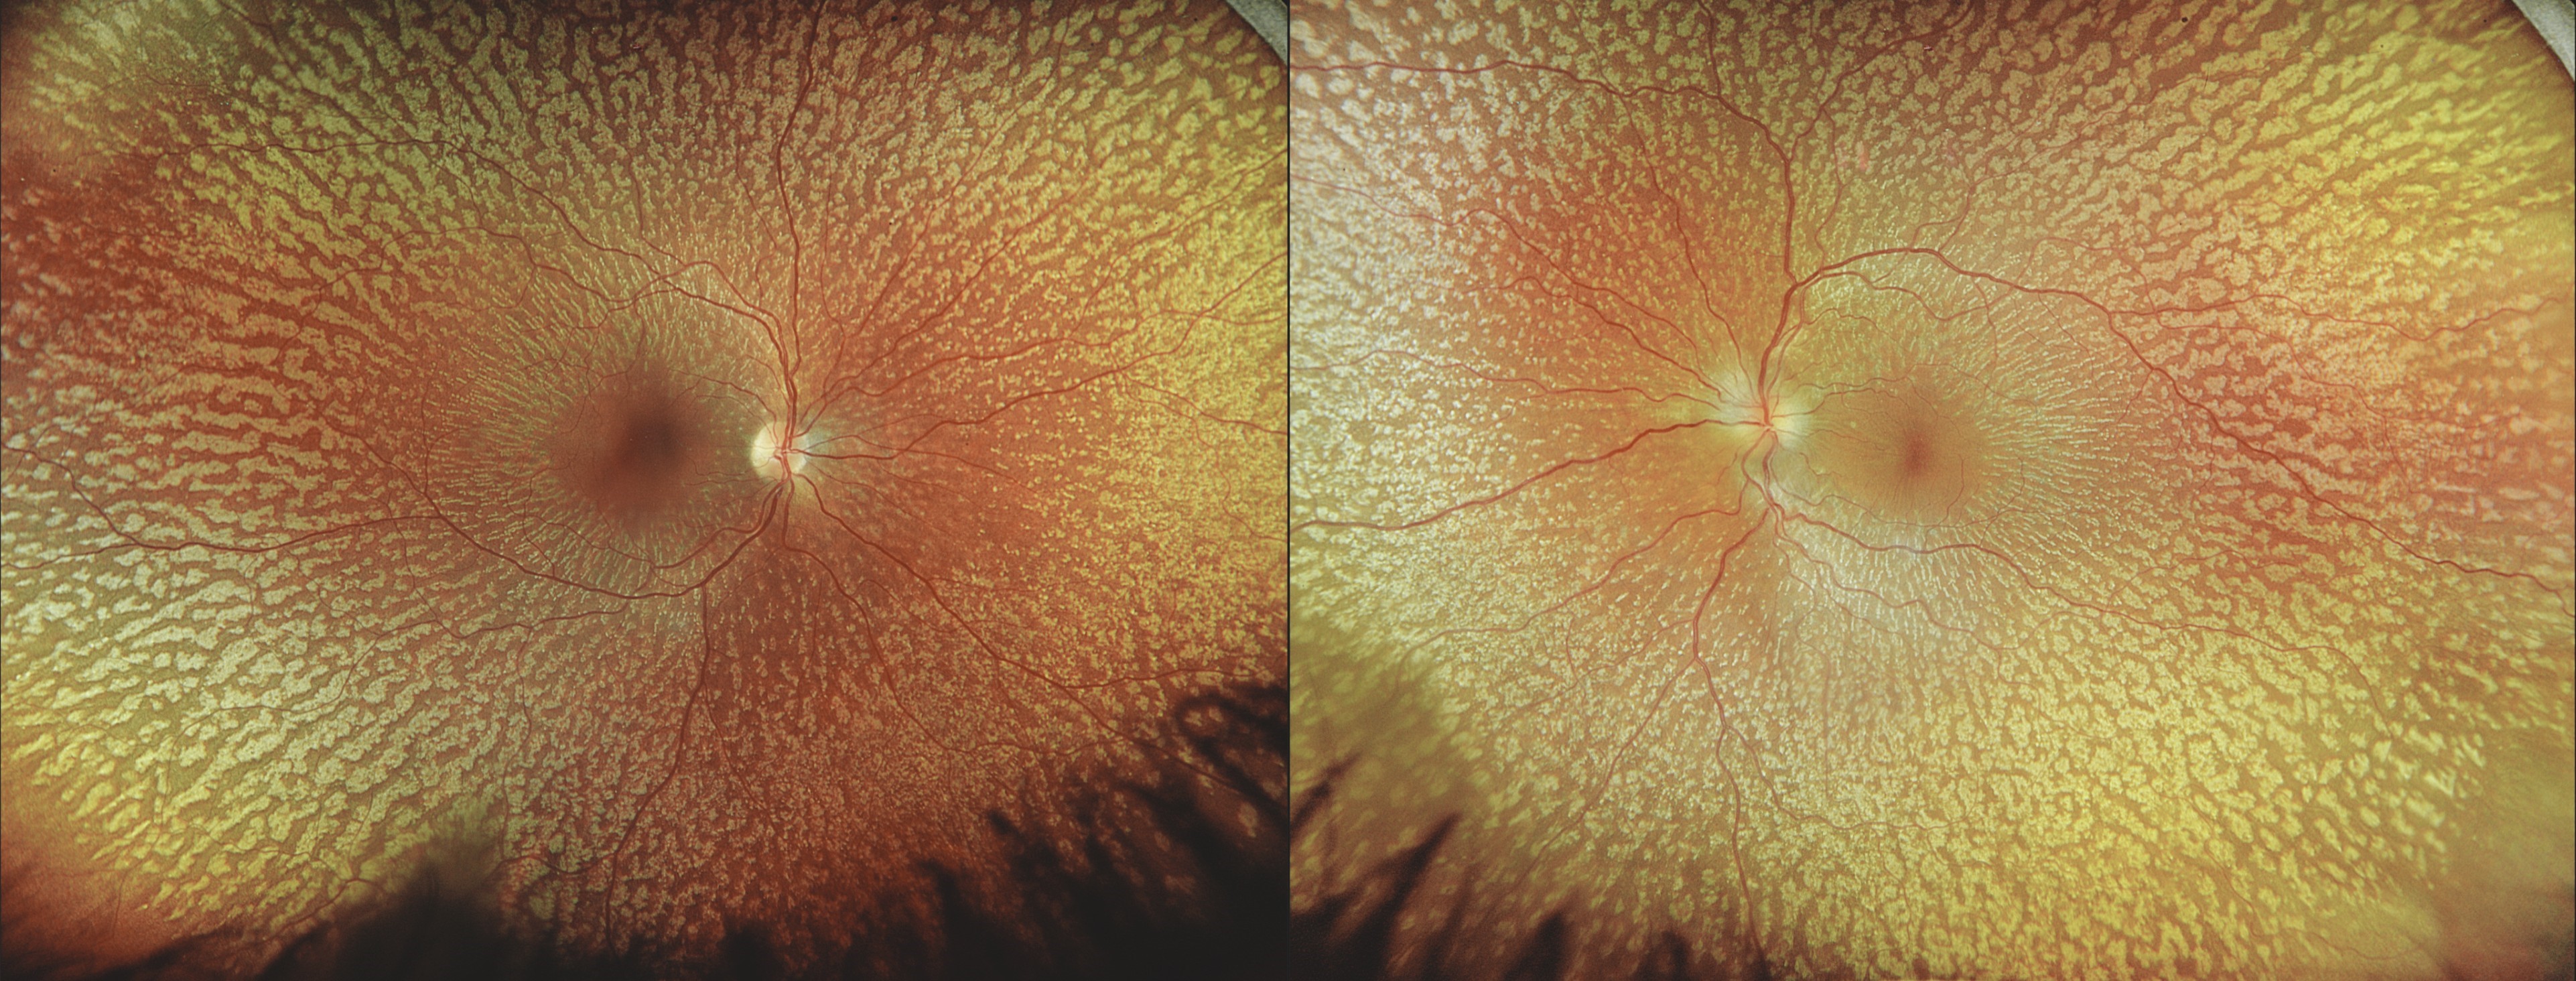

A GALAXY BENEATH THE GAZE : STARRY BUT SILENT Benign familial fleck retina

Author: Dr. ABHISHEK G NAIR

View